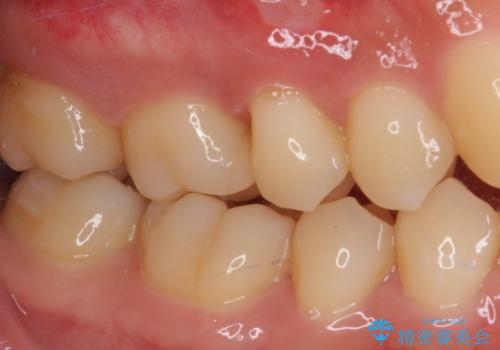

フロスが引っかかる セラミックインレーによるむし歯治療

- ウェブサイトの症例(https://seimitsushinbi.jp/case/9473/)を見て、同じようにフロスが引っかかるとのことで来院された患者様です。

虫歯を除去した後、セラミックインレーにて修復治療を行うこととしました。

セラミックインレー装着後はフロスの引っかかるストレスから解放され、患者様には大変満足していただきました。